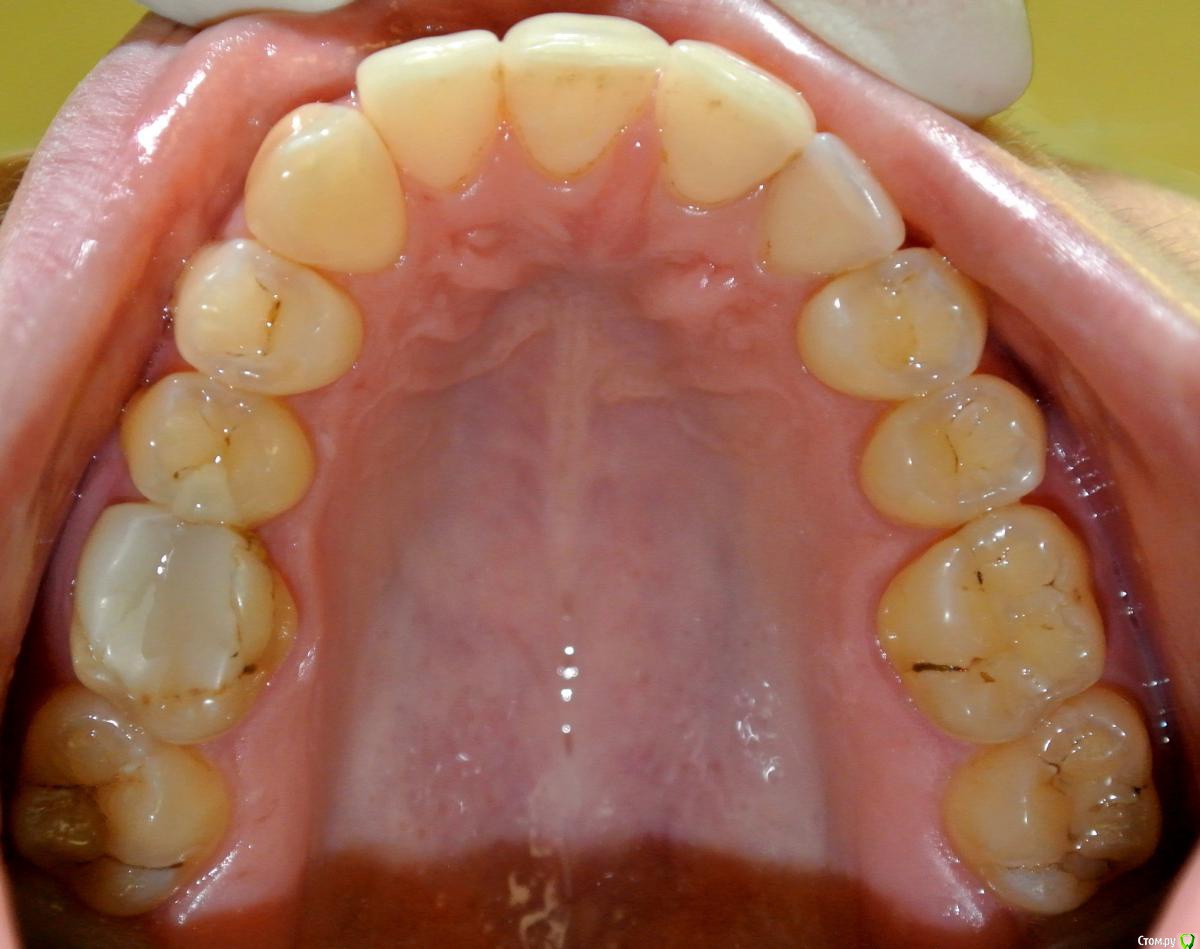

Yana guapa Опубликовано 2 апреля, 2015 Поделиться Опубликовано 2 апреля, 2015 Хорошо бы фото с улыбкой в полный фас , т.к. средние линии лица, носа, губ, ВЧ и НЧ все между собой могут не совпадать. Судя по данным фото, смещение средней линии ВЧ присутствует, но в большей степени здесь играет роль уплощение ВЧ справа. Поэтому и расширять в данном месте нужно, устранять асимметрию ВЧ, с восстановлением дефекта з/р (имплантацией клыка) . Вся ВЧ сужена. Раскрывать под клык надо. Ссылка на комментарий

Dina_N Опубликовано 4 апреля, 2015 Автор Поделиться Опубликовано 4 апреля, 2015 дополнительные фотографии Ссылка на комментарий

229KAMA Опубликовано 11 апреля, 2015 Поделиться Опубликовано 11 апреля, 2015 Пациентка Н., 30 лет. Жалоба на смещение средней линии верхнего зубного ряда. Из анамнеза: зуб 1.3. удален в возрасте 9 лет (ох уж эти удаляльщики). Как можно скорректировать положение средней линии?DSC_7521.JPGDSC_7522.JPGDSC_7524.JPGDSC_7525.JPGDSC_7526обр.jpgDSC_7527 обр.jpgСкажите пожалуста Я вот прочитал "1.3. удален в возрасте 9 лет" -это постоянный клык вроде так по номеру и квадранту (постоянный). А на фото Я вижу его на предоставленных фотографиях , что он стоит в челюсти. Или Я вижу , что то не так. Если ошибаюсь то возможно по не опытности ? приношу свои извинения. Ссылка на комментарий